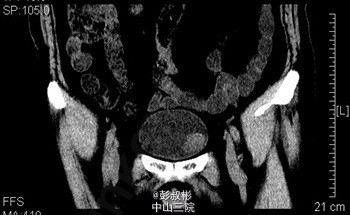

膀胱肿瘤电切实录--看看膀胱癌长这样

主诉 病史

68岁,男性,反复肉眼血尿3个月。盆腔CT:膀胱左前下侧壁约20×21×21 mm肿块,考虑膀胱癌可能性大。术前诊断:膀胱癌。患者合并心肺功能不全,要求保留膀胱。